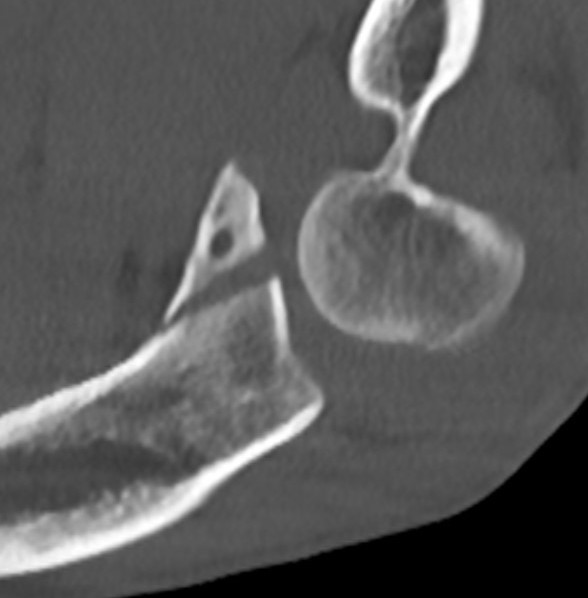

Elbow dislocation with coronoid process fracture

Coronoid process

Coronoid is the most important portion of ulno-humeral articulation

- provides anterior buttress

- attachment of capsule and brachialis

- anterior band of the MCL attaches to it

Regan and Morrey classification of transverse coronoid fractures

Elbow stability related to size of coronoid fragment

| Type I | Type II | Type III |

|---|---|---|

| Small coronoid process fracture | 50% of coronoid process | > 50% coronoid process |

| Usually stable |

Capsular attachment Elbw may be unstable |

Capsule + MCL attachment Elbow unstable

|

O'Driscoll classification anteromedial coronoid facet fractures

| Type I | Type II | Type III |

|---|---|---|

| Transverse fractures | Anteromedial facet fractures | Basilar fractures |

| Lasso suture fixation |

Lasso suture fixation - small Medial buttress plate / screws - large |

Dorsal +/- medial plate |

Anteromedial coronoid facet fragment

- associated with varus posteromedial rotational force

- associated with tear of lateral ulna collateral ligament (LUCL)